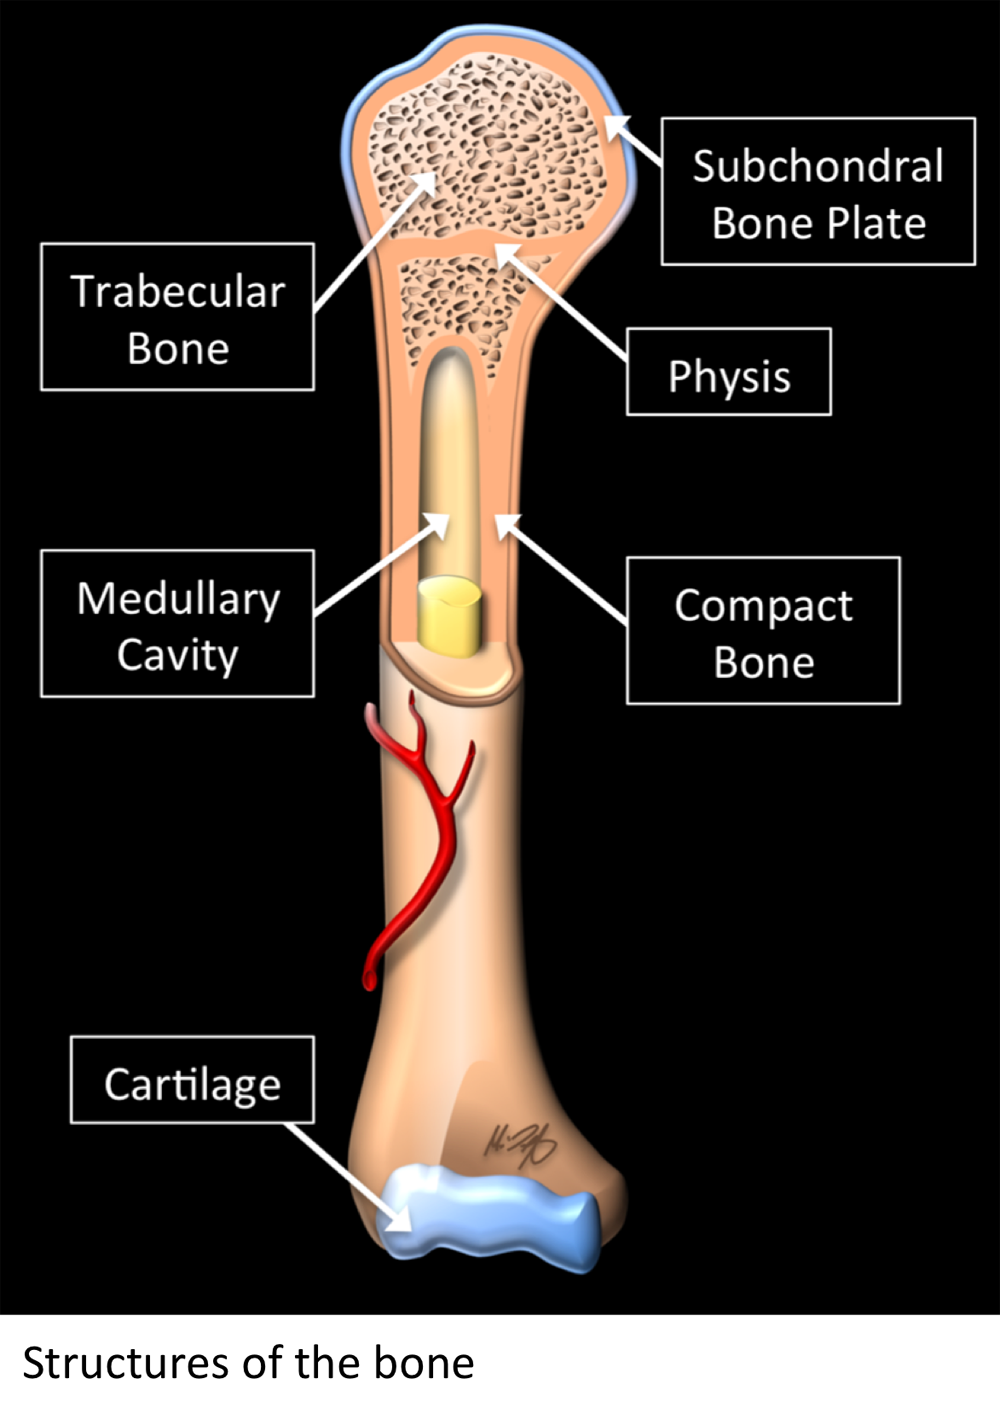

What is MRI used for in the bone ?

- MRI allows us to see many of the different structures in the bones.

- Several injuries or diseases affecting those structures can be diagnosed using MRI.

- Common things affecting bones include osteoporosis, tumors, fractures, osteoarthritis, among others.

Why Translational MRI of the bone?

- In the bone, as in many other tissues of the body there are certain structures that can’t be seen (they look black or dark) with the standard MRI.

- There are new “software” programs that allow us to see structures with different contrast (bright versus dark).

- In the bone these “invisible” or dark structures include cortical bone, subchondral bone plate and vertebral endplate.